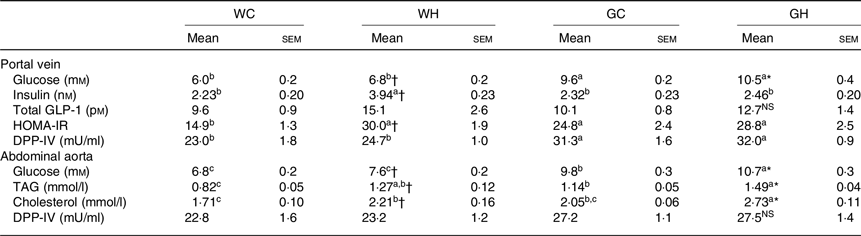

Plasma parameters after 26-week feeding period

After a feeding period of 26 weeks, fasting glucose levels in HFS diet feeding groups (WH and GH) were higher than those of the respective control diet feeding groups (WC and GC) both in portal vein and abdominal aorta blood samples (Table 4). Regardless of the diet consumed, the GK rats showed higher fasting glucose levels compared with the Wistar rats. The WH group showed significantly higher and slightly but not significantly higher levels of fasting insulin and GLP-1, respectively, in comparison with the WC group, whereas the GH group showed similar levels to those of the GC group (Table 4). These results were consistent with postprandial glucose, insulin and GLP responses after the 24-week feeding period (Figs. 1–3). Fasting TAG and cholesterol levels in the abdominal aorta had similar trends with fasting glucose concentrations (Table 4). DPP-IV activity in GK rats was significantly higher in the portal vein compared with that of Wistar rats. Diet did not affect DPP-IV activity both in Wistar and GK rats (Table 4).

Table 4. Plasma parameters after 26-week feeding period‡ (n 7–9 rats)

(Mean values with their standard errors)

WC, Wistar rats fed a control diet; WH, Wistar rats fed a high fat/high sucrose diet; GC, Goto-Kakizaki rats fed a control diet; GH, Goto-Kakizaki rats fed a high fat/high sucrose diet; GLP-1, glucagon-like peptide-1; HOMA-IR, homeostatic model assessment of insulin resistance; DPP-IV, dipeptidyl-peptidase IV.

a,b,c Mean values in a row with unlike superscript letters are significantly different (P < 0·05, Tukey–Kramer’s test).

* Significant differences between mean values of the GC and GH groups (P < 0·05, Student’s t test). NS indicates that there was no significant difference between the treatments.

† Significant differences between mean values of the WC and WH groups.

‡ Wistar and diabetic Goto-Kakizaki rats were fed either the control diet or the high fat/high sucrose diet for 26 weeks. Blood samples from the portal vein and abdominal aorta were collected under sodium pentobarbital anaesthesia (50 mg/kg body weight) after an overnight fast.